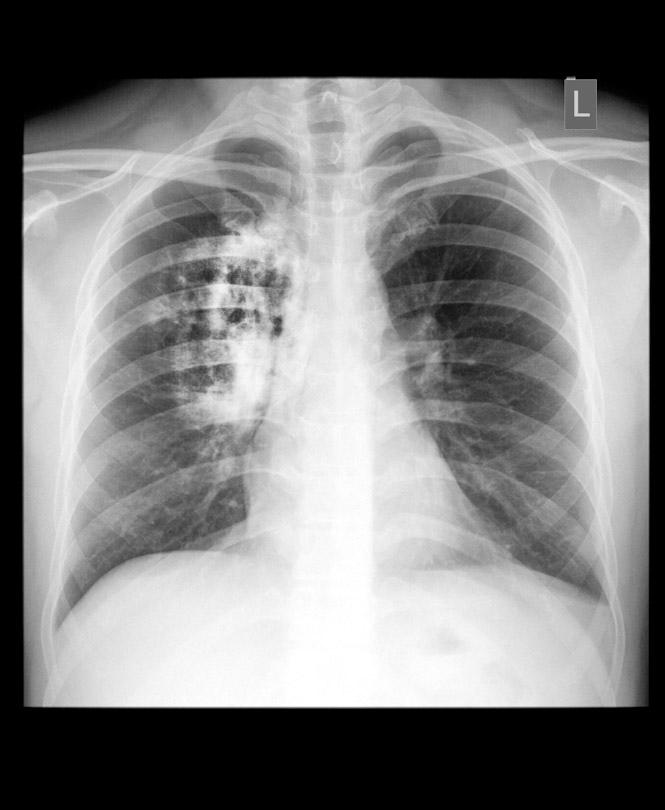

Un estudio pone de manifiesto las desigualdades socioeconómicas en la mortalidad por cáncer de pulmón

El Día Mundial del Pulmón, celebrado el 25 de septiembre, este año hace énfasis en la reducción de las desigualdades socioeconómicas y geográficas en las enfermedades respiratorias. Entre las enfermedades respiratorias más importantes se encuentra el cáncer de pulmón, el cáncer que más muertes causa en España.

Un estudio del grupo de investigación A17- Epidemiología, Prevención y Control del Cáncer del Instituto de Investigación Biosanitaria de Granada (ibs.GRANADA) ha caracterizado las desigualdades socioeconómicas en la mortalidad por cáncer de pulmón en España. Se han analizado todas las muertes por esta enfermedad ocurridos en nuestro país del año 2011 al 2017, en relación con el nivel de la riqueza o pobreza de la zona en la que vivían las personas, su sexo y edad.

Los resultados demuestran un patrón claro de diferencias entre hombres y mujeres que se mantiene estable durante el periodo de estudio y tanto en zonas rurales como urbanas. "Entre los hombres, la mortalidad por cáncer de pulmón es más alta en aquellos que viven en las zonas más pobres del país. Al contrario, entre las mujeres la mortalidad por cáncer de pulmón es más alta entre las que viven en las zonas más ricas", señala Daniel Redondo-Sánchez, investigador del ibs.GRANADA y del CIBERESP y primer firmante del trabajo.

Para María José Sánchez, profesora de la Escuela Andaluza de Salud Pública, investigadora principal del grupo y directora científica del ibs.GRANADA, hay un consenso experto de que estas diferencias se deben en gran parte al consumo de tabaco, que causa alrededor de 90% de los cánceres de pulmón. Según Sánchez, "la mortalidad por cáncer de pulmón es más alta en los hombres que en las mujeres, en parte debido a su mayor exposición histórica al tabaquismo". Sin embargo, en los últimos años se observa un incremento importante en la mortalidad por cáncer de pulmón entre las mujeres, "que pensamos que refleja su mayor incorporación al tabaquismo después de los años 70, especialmente entre las mujeres más ricas o con más estudios", manifiesta la investigadora.